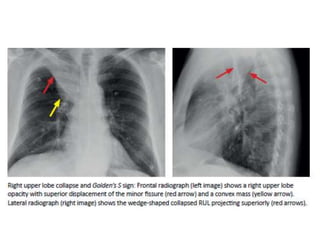

COLLAPSE

• Direct signs of atelectasis are from lobar volume loss

and include:

-Displacement of the fissures

-Vascular crowding.

• Indirect signs of atelectasis are due to the effect of

volume loss on adjacent structures

-Elevation of the diaphragm.

-Rib crowding on the side with volume loss.

-Mediastinal shift to the side with volume loss.

-Overinflation of adjacent or c/l lobes

-hilar displacement

COLLAPSE • Direct signsof atelectasis are from lobar volume loss and include: -Displacement of the fissures -Vascular crowding. • Indirect signs of atelectasis are due to the effect of volume loss on adjacent structures -Elevation of the diaphragm. -Rib crowding on the side with volume loss. -Mediastinal shift to the side with volume loss. -Overinflation of adjacent or c/l lobes -hilar displacement